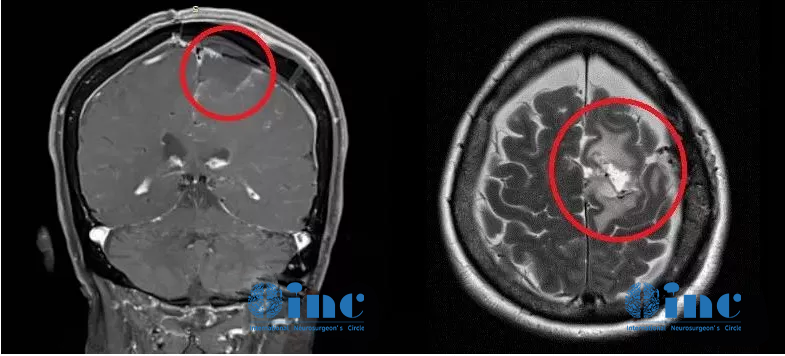

家人辗转求医最终找到INC德国巴特朗菲教授,王女士的治疗才迎来转机。在教授所在的德国INI国际神经学研究所、由INC德国巴特朗菲教授主刀的一场高质量手术直接全部切除了患者大脑深部复杂部位的脑膜瘤,她大脑中的“定时炸弹”被彻底摘除。如今手术已过去了1年半,从其术前MR、刚手术后的MR、术后1年半多的MR可以清楚看到未见复发迹象,患者现在一切生活如常,幸福的晚年生活不必再被可怕的肿瘤打扰。

术后一年半MR

脑膜瘤的预后情况、并发症的发生率及恢复时间与肿瘤位置、生长特点、术者的技术经验等息息相关,对于解剖位置比较复杂的脑膜瘤,例如枕骨大孔区、斜坡位置深,风险高,可操作空间狭窄,切除肿瘤必须跨过很多神经,容易损伤神经及脑干。手术难度大,导致切除不干净,如果强行切除,神经损伤引起瘫痪等副作用的风险就急剧升高。

例如此病例,大脑镰和矢状窦的脑膜瘤经常侵犯重要大血管甚至存在严重黏连,导致肿瘤不易全切或者容易伤及大血管,造成严重的神经损伤,这样因为肿瘤侵及矢状窦容易出血,切除这血管上的肿瘤难度高、风险大。因为它们会影响手术的可及性并确定是否可以完全切除,并保证患者正常的神经功能不受损伤。而寻找世界知名神经外科专家的手术治疗,为的就是对于高难度手术的高切除率、低风险、低副作用,而且脑膜瘤如果第一次手术能够安全全切,那么复发的可能性就越低,无进展生存期(PFS)就越长,总体预后(Prognosis)和总生存期(OS)就越好,避免术后神经功能损伤、恢复不佳的经济及社会心理负担等,生活质量更大程度地得到保障。